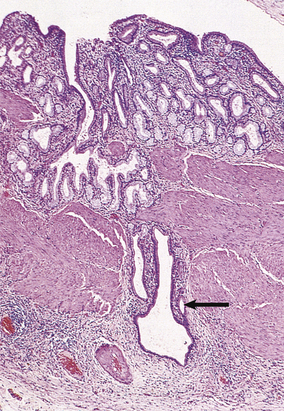

Bile accumulates within the liver, initially in the canaliculi (Fig. 16.8) and later within the intrahepatic bile ducts. Rupture of these may result in extravasation of bile into the adjacent liver tissue; the resulting necrosis has been misnamed as a ‘bile infarct’. The portal tracts are oedematous and infiltrated with neutrophil polymorphs. The hepatocytes at the edge of the portal tract undergo ductular metaplasia. Cholangitis is recognised histologically by the presence of neutrophil polymorphs in the bile ducts.

image

Fig. 16.8 Histology of intrahepatic cholestasis in biliary obstruction. The bile canaliculi are stuffed with stagnant brown bile that cannot be discharged from the liver because the common bile duct is blocked by a gallstone. Similar appearances result from viral hepatitis and some adverse drug reactions.

Repeated episodes of biliary obstruction lead to portal tract fibrosis and nodular regeneration of the liver cells—secondary biliary cirrhosis.